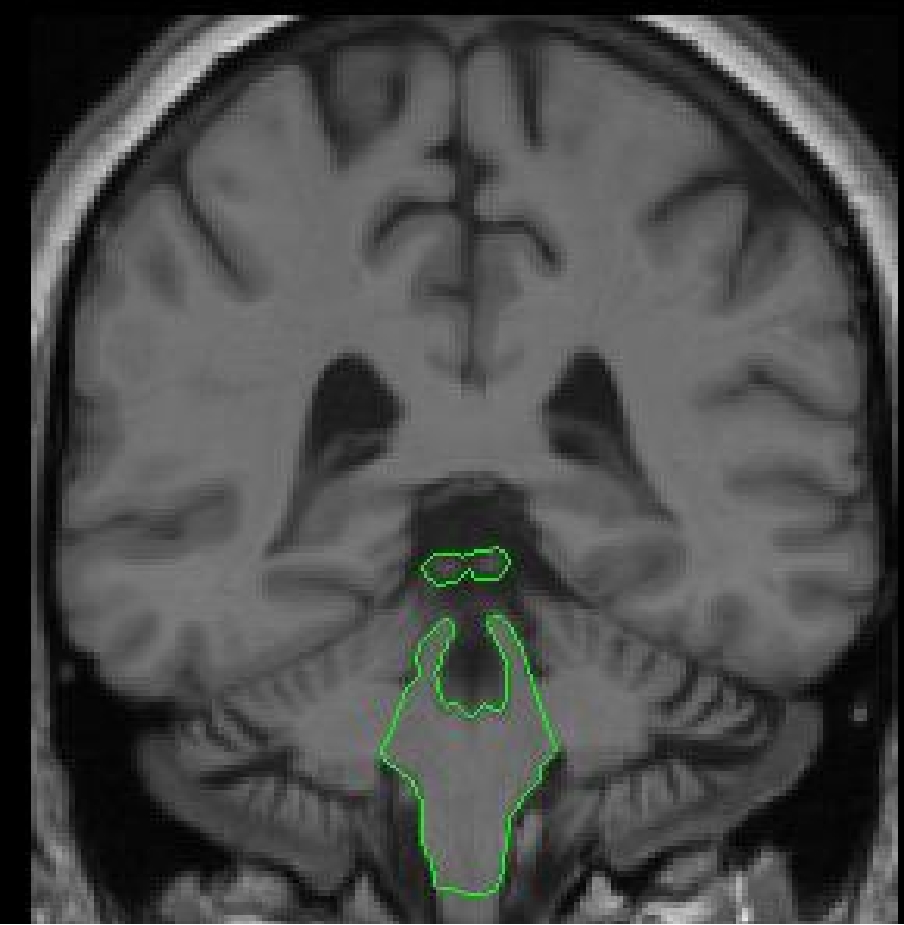

Part IV - Cerebellum appears

At its anterior extent, the cerebellum shares its medial borders with the brainstem.

The lateral extremities of the brainstem are no longer taken as part of the

brainstem outline. They are extracted separately as cerebellar exterior and

as cerebellar white matter. With the contrast increased it is easy to see the

division between cerebellar white matter and brainstem. This division can be

manually drawn in or it may be possible to use the contour function. The next

slices will have cerebellum present and these lateral extremities will again

be extracted as cerebellar white matter.

Part V - The colliculi appear

In the more posterior slices when the superior brainstem line is no longer

visible, it is necessary to draw in the superior and inferior colliculi manually

or with the use of the contour function. There may be a slice or two where

the colliculi are not yet attached to the brainstem, in this instance extract

them as a separate outline which will still be labeled brainstem.

In this area be careful to exclude the pineal gland from the volume of the

brainstem.

The inferior border in the more posterior extent (where the medulla is connected

to

the spinal cord) depends on the inferior brainstem line drawn for the inferior

border of the brainstem. Draw a line that bisects the inferior brainstem line

(appearing as a dot). Everything above this line will be brainstem, and everything

below it will be spinal cord and considered outside of the brain.

Be sure to always attach the 4th ventricle' to the brainstem exterior to exclude it from the volume of the brainstem.